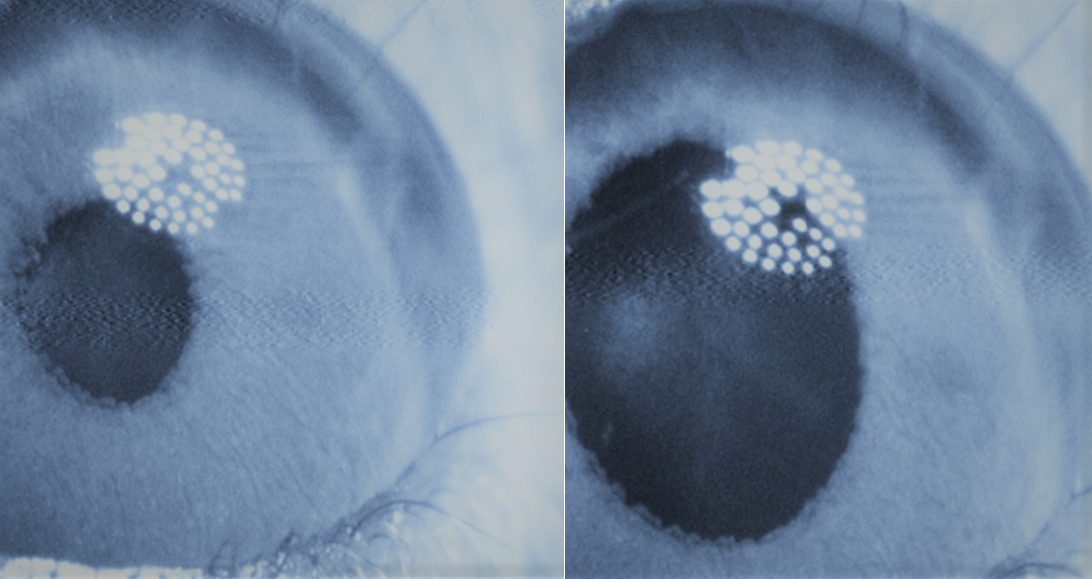

Cuando se probó en ratones ciegos, cuyas pupilas no responden a la iluminación, la molécula adrenoswitch-1 provocó una dilatación de la pupila que se revirtió al retirar la fuente de luz activadora. En los animales silvestres, inhibió el reflejo de contracción de la pupila al activarla con luz violeta.

Imagen: El grado de dilatación de la pupila está regulado por α-adrenoceptores ubicados en el músculo dilatador del iris. La exposición a la luz intensa induce una contracción espontánea de la pupila como mecanismo reflejo para proteger la retina. Adrenoswitch-1, un agonista fotocrómico α-adrenérgico (A), provoca una respuesta en ratones ciegos tras la activación con luz violeta (B). En animales silvestres, el compuesto inhibió el reflejo pupilar causado por la luz violeta (trazo púrpura), mientras que la respuesta a la luz visible se mantuvo (trazo verde) (C) Fuente: Angewandte Chemie International Edition, 2020.